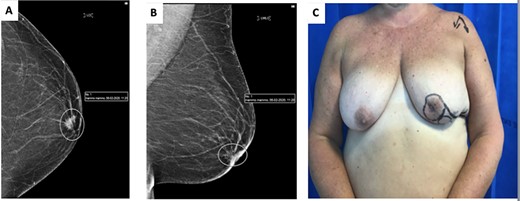

(A) Image showing 1-week post-operative results; note the maintenance of neo-nipple to IMF crease distance of 6 cm. (B) Contralateral breast showing location of standard Grisotti disc; note the relatively short NAC-IMF of 3 cm that would result if this technique were undertaken.

As per standard procedure [2], the undermining of the lateral remaining glandular tissue was then performed to facilitate the advancement, rotation and medialization of the glandular tissue in order to increase the projection of the breast (Fig. 3A and B). The patient had good aesthetic results and maintenance of an acceptable neo-nipple to IMF distance of 6.5 cm (Fig. 4).

Grisotti’s original description [7] involved the creation of a circular disc of skin inferior to the NAC. This dermoglandular flap is then advanced and rotated into the defect. Based on this description, however, it can be inferred that this flap is not ideal for patients with a short NAC to IMF distance, as this flap will invariably shorten the NAC to IMF distance further. In our presented case, we propose a technical modification that allows adequate reconstruction, even in patients with a relatively short NAC to IMF distance (Fig. 4B). The inferolateral placement of the disc still allows adequate rotation and advancement of the circular disc of skin used to replace the areola, avoiding the shortening of the NAC to IMF distance and equally maintaining a natural projection and an aesthetically pleasing contour of the breast (Fig. 4).